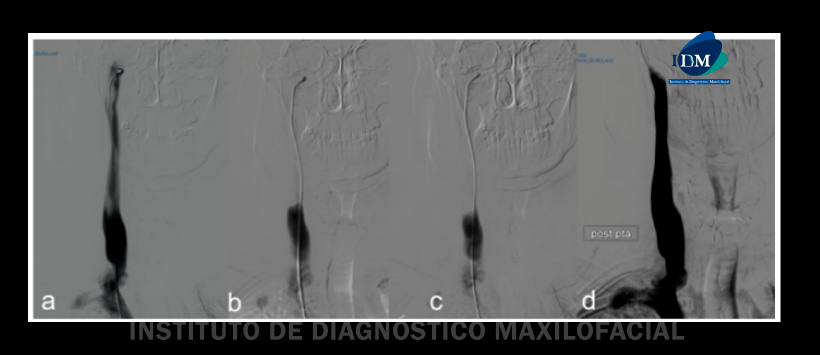

El clásico, caracterizado principalmente por dolor y disfagia, y la variante carotídea caracterizada por dolor y algunas veces por isquemia cerebral. Observamos otra variante caracterizada por un alargamiento de la apofisis estiloides adyacente al proceso transversal de C1, causando una compresión significativa de la vena yugular interna. (Figura 1)

En el grupo la variante carotídea clásica se caracterizó por dolor ipsilateral con respecto a la variante yugular. La angiografía por tomografía computarizada con fase venosa extendida a las venas del cuello y la reconstrucción de imágenes es muy recomendable como técnica imagenologica, complementada por ultrasonido Doppler. (Figura 2)

Figura 1: a) Presión venosa antes de la cirugía, b) Presión venosa después de la cirugía.